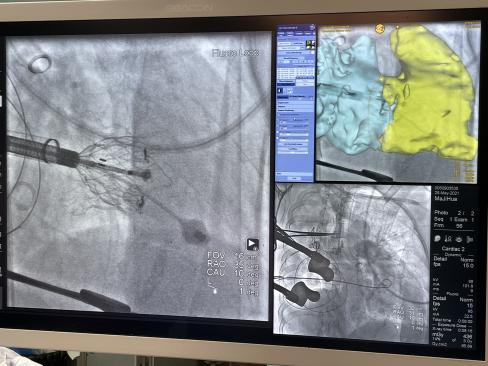

图3.心外科瓣膜中心创新术中虚拟影像融合技术助力介入三尖瓣植入手术

患者唐某某,68岁,起搏器术后重度三尖瓣关闭不全,双下肢浮肿和胸腔积液,继往肝硬化和多脏器功能不全病史难以耐受常规开胸手术。三尖瓣介入瓣膜植入需要明确三尖瓣前叶和瓣环位置,但是三尖瓣疾病几乎没有钙化,透视下完全没有显影,常规介入三尖瓣植入手术需要依赖不断造影以及超声反复不同切面观察定位。而术中利用虚拟影像融合技术可以精准定位瓣环平面,释放心房伞盘才不至于误入右心室或者介入瓣膜腰部误入右心房。介入手术虚拟影像融合技术大大简化了手术植入流程,减少了造影剂使用,进一步提高了手术成功率。